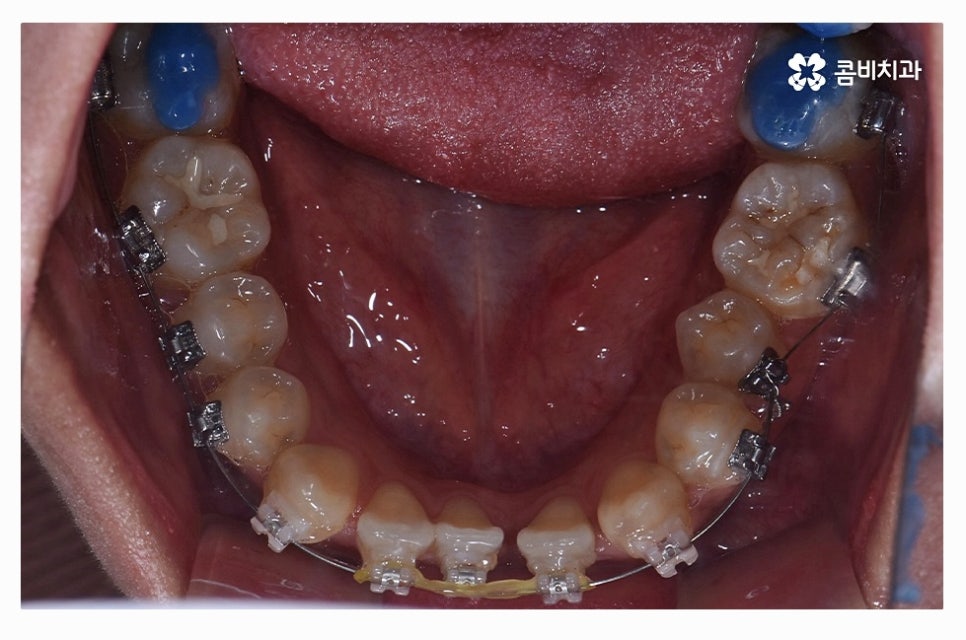

치아교정은 장기간의 치료 계획을 세워야 하기 때문에

교정 효율성이 좋고, 상대적으로 통증이 적으며 관리가 편리한

클리피씨 장치가 보편적으로 많이 활용되고 있으며

치열 상태나 환자의 니즈에 따라서 심미성이 높은 설측교정이나

투명교정이 활용되는 경우도 있어요.